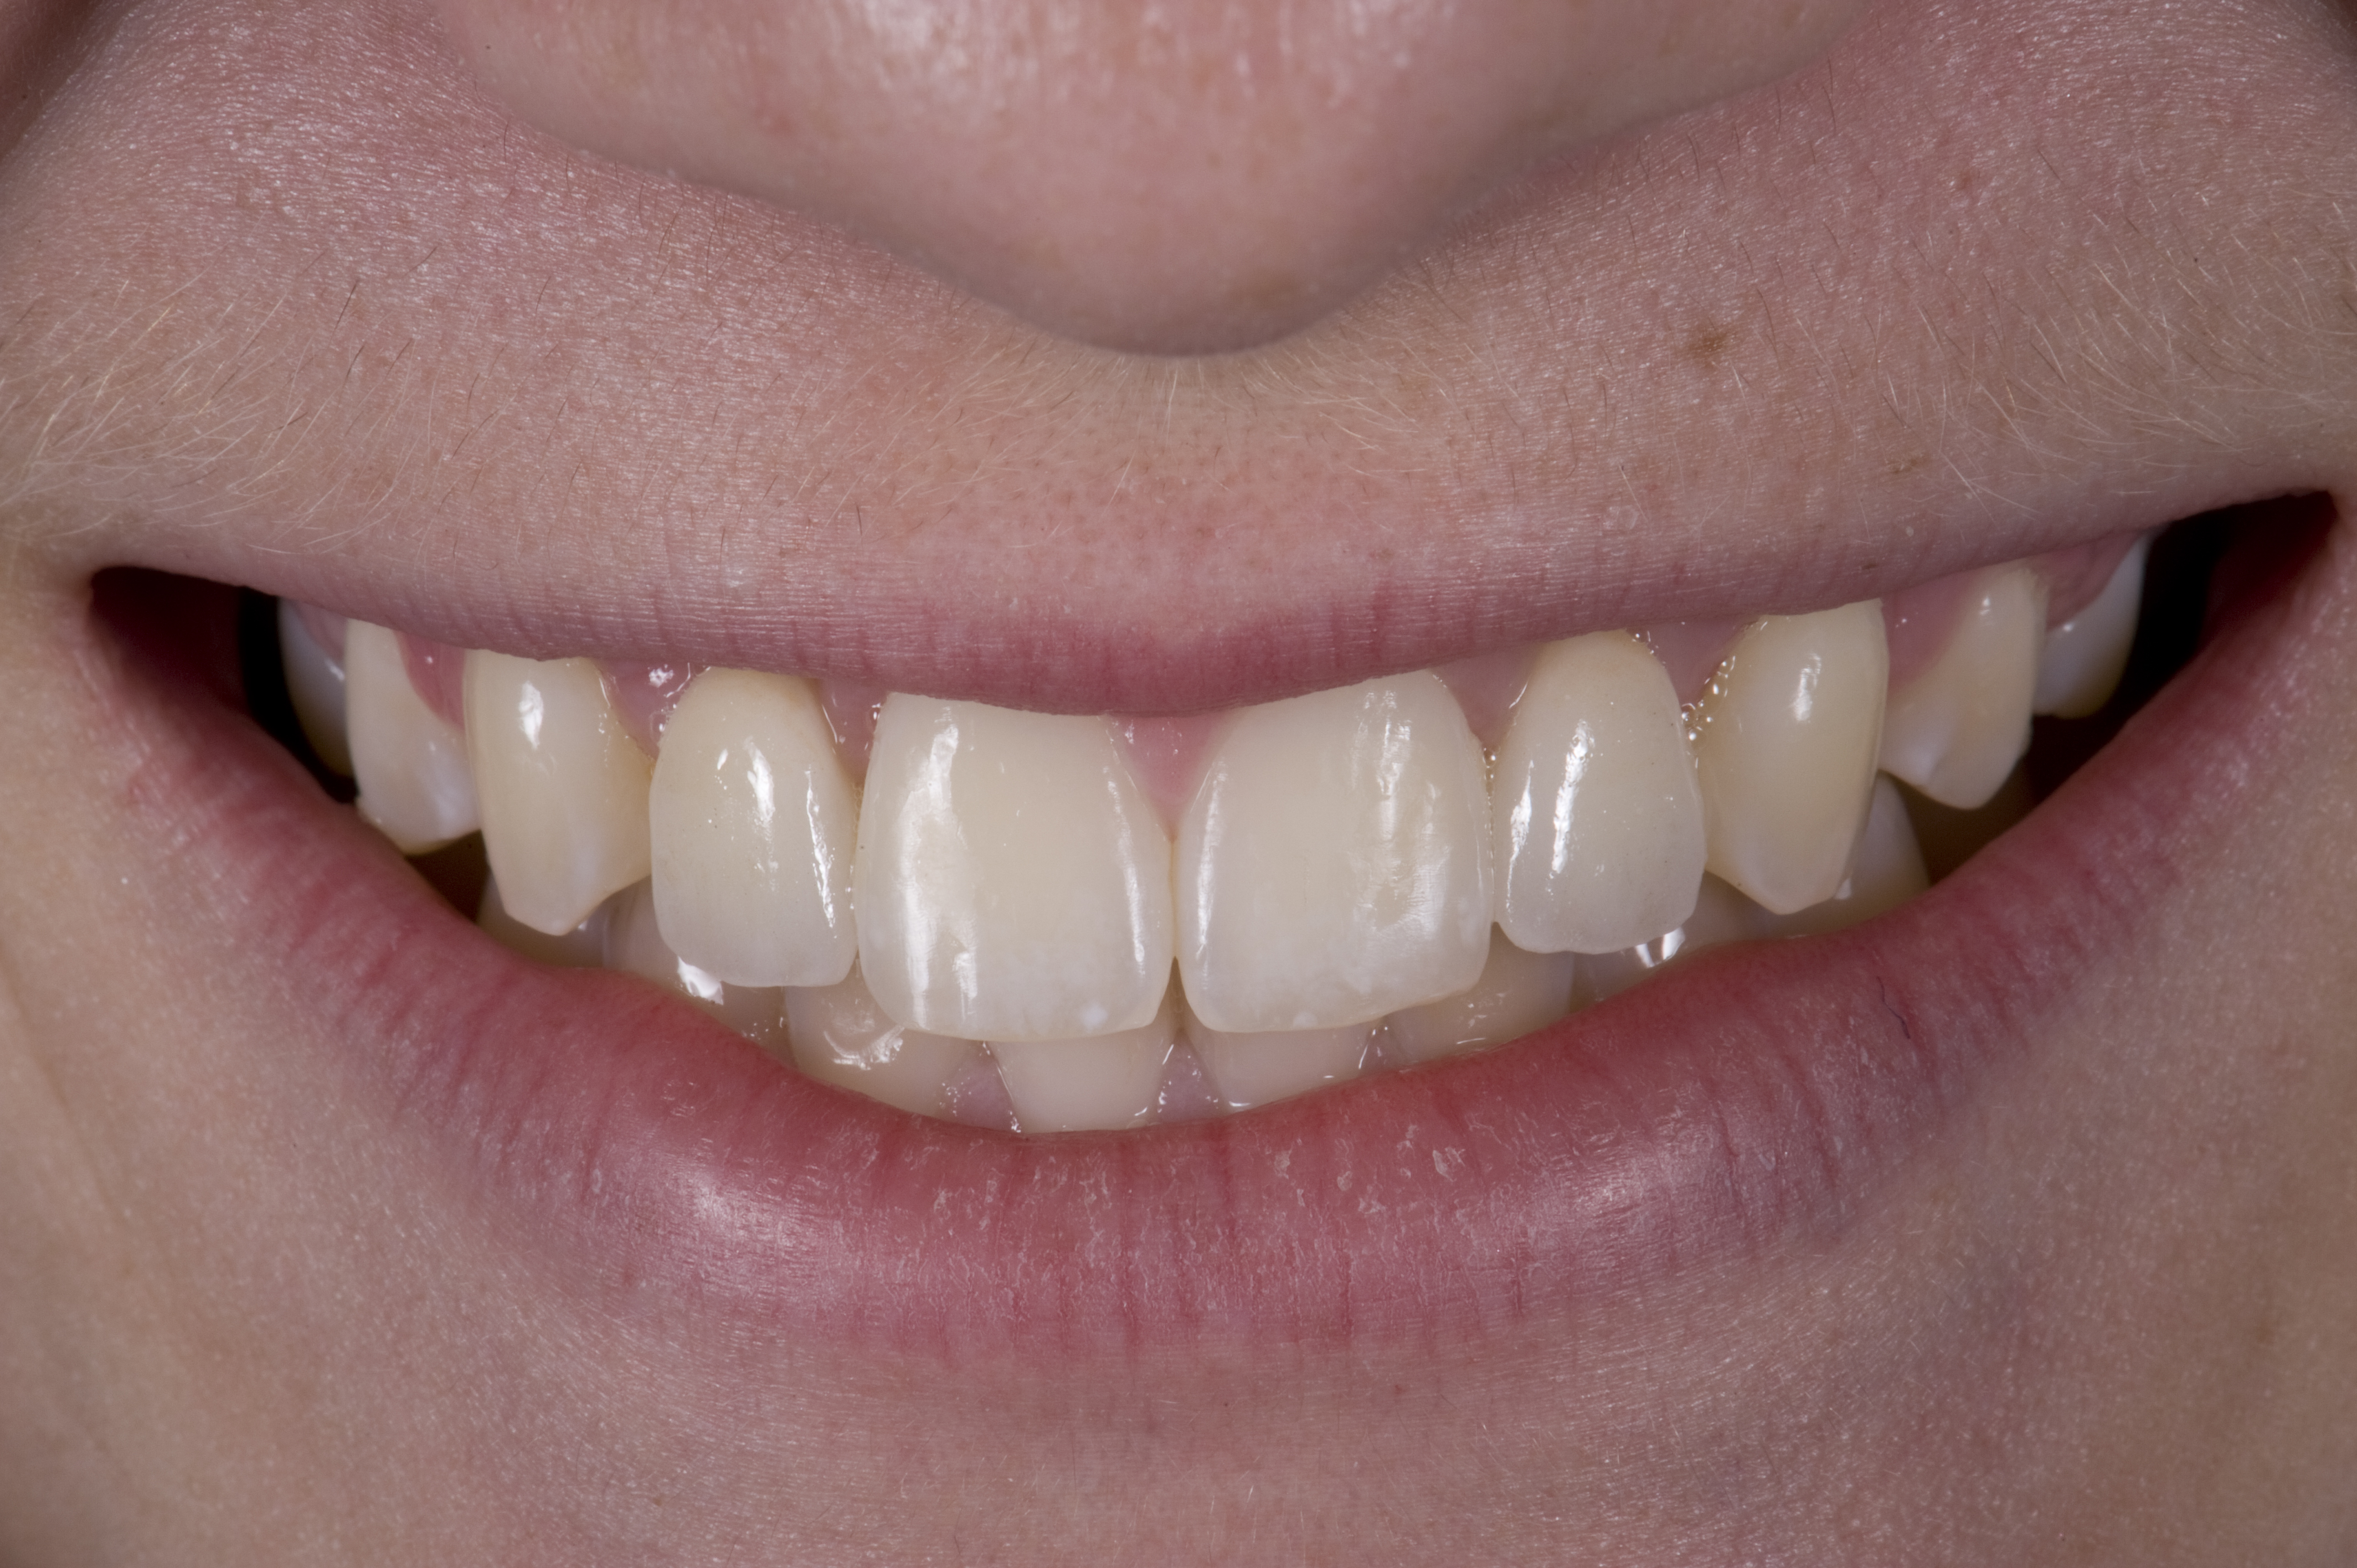

(12.) 15-year-old girl after orthodontic therapy idealized maxillary lateral incisor spaces.

Figure 12